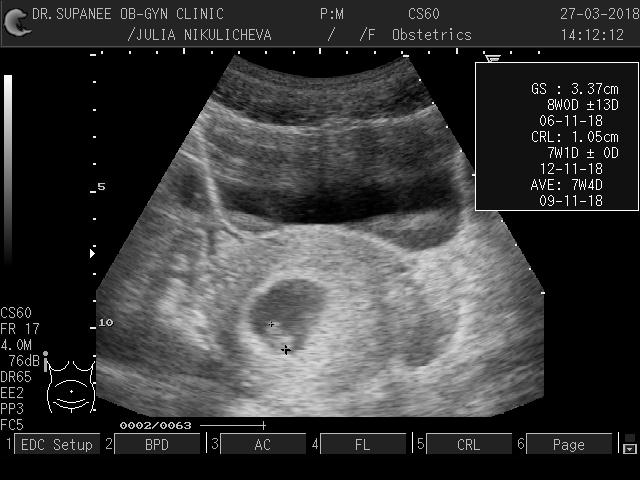

Наше УЗИ 😍

Говорят, на этой неделе уже формируются черты лица😍😙самого любимого лица в мире❤